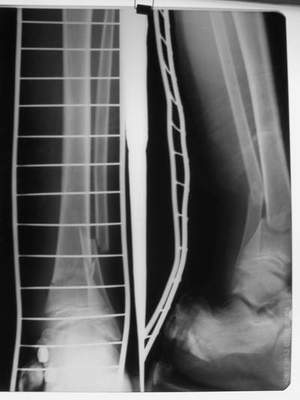

Перелом костей н\3 правой голени со смещением. Перелом большеберцовой кости можно охарактеризовать как компрессионно-оскольчатый.

В январе 2005: варусная деформация н\3 голени, болевой с-м, комбинированная контрактура г\стопного сустава, нейропатия м\берцового нерва сохраняется слабость разгибания 1 пальца.

Операции: 1 Клиновидная резекция на вершине деформации м\берцовой кости.

2 Тугоподвижный ложный сустав н\3 б\берцовой кости. Рубцы выполняющие пространство между отломками, канал проксимального отломка иссечены.

Одномоментное устранение деформации, остеосинтез Г-образной пластиной.

Так как речь зашла непосредственно о травме, см этапные

снимки. Как все было